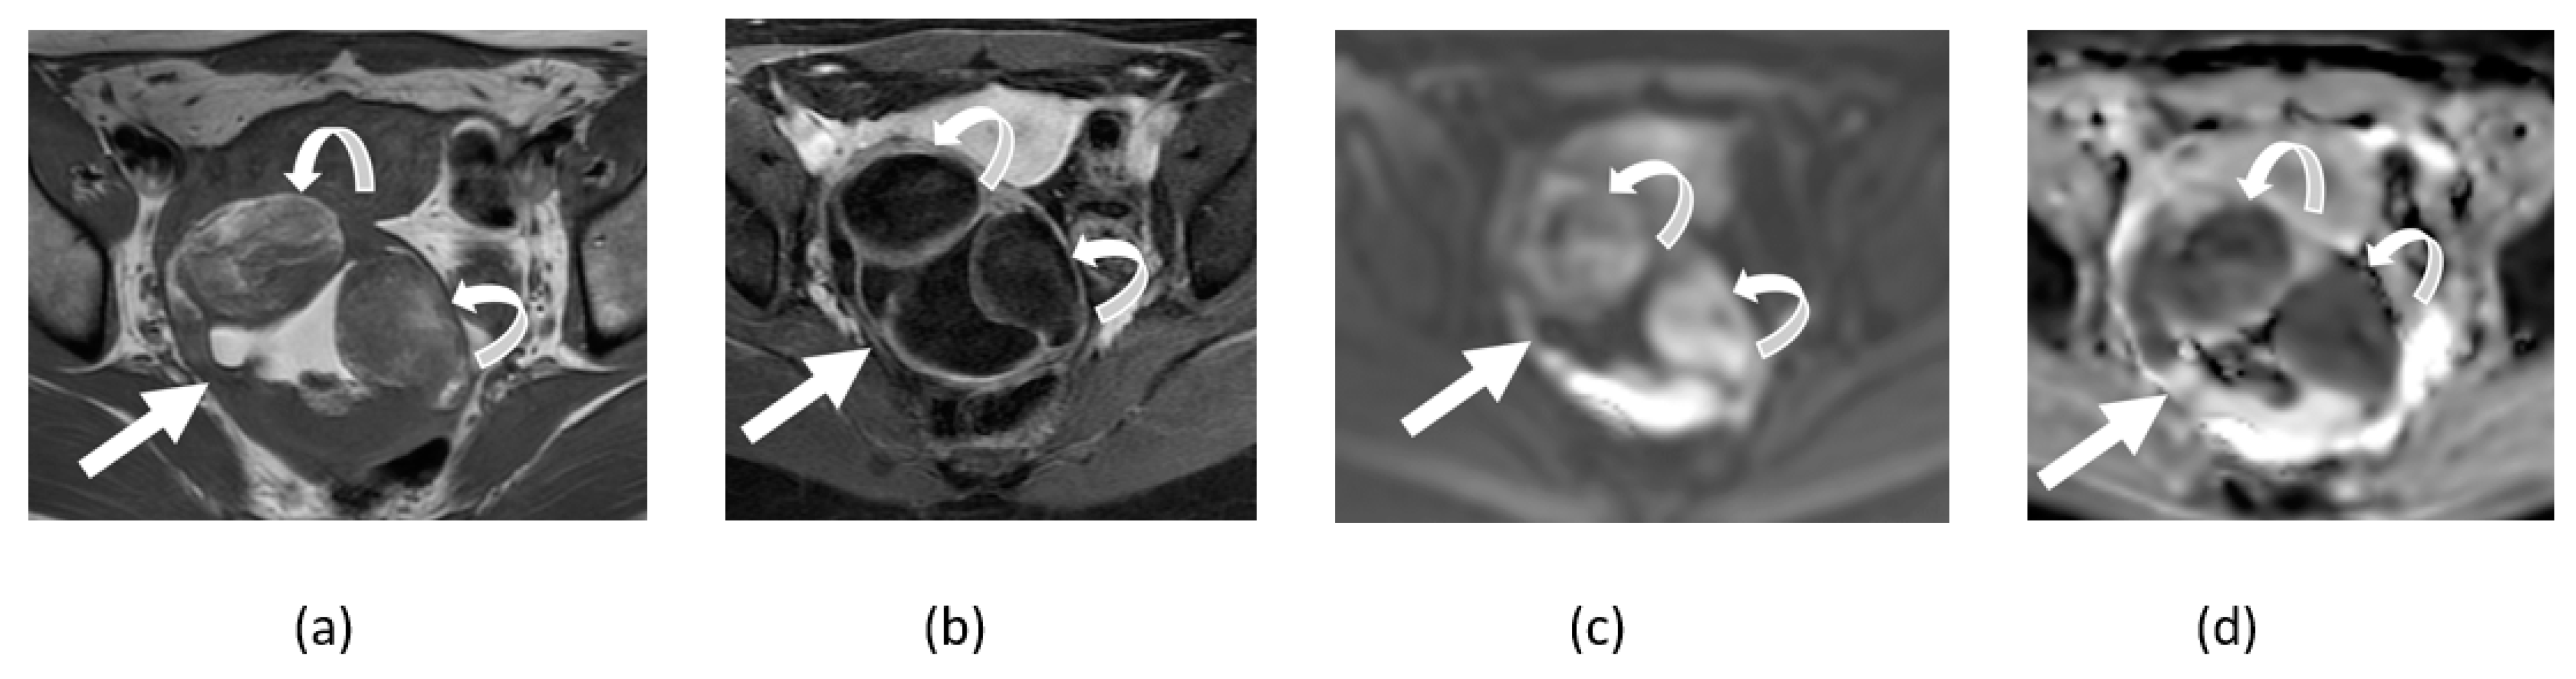

5.1. T2 Shine-Through Effect

5.2. T2 Blackout Effect

5.3. Diagnostic Pitfalls